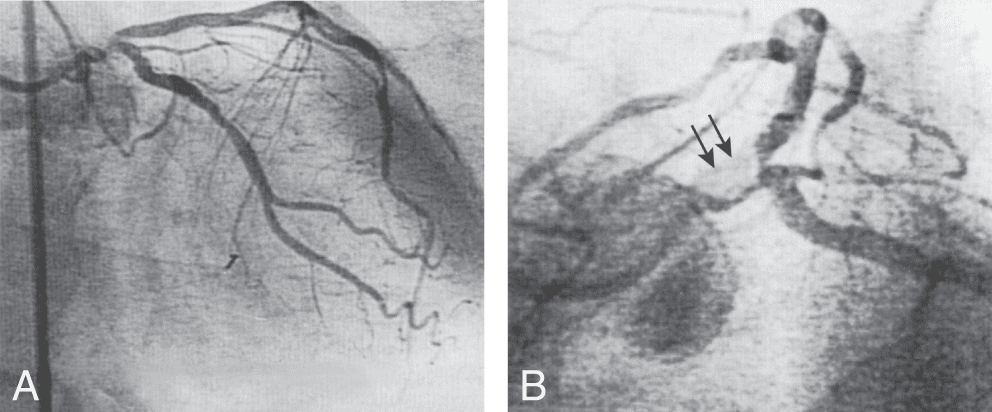

Le débit coronaire est rythmé par la contraction du myocarde. Au niveau de la paroi du ventricule gauche le débit est à 80 % diastolique. Pour la paroi du ventricule droit, il se répartit à égalité entre la diastole et la systole (fig. 3.2A). Au repos, le débit coronaire est d’environ 0,8 à 1 ml/min par gramme de myocarde pour le ventricule gauche et de 0,6 à 0,7 ml/min par gramme de myocarde pour le ventricule droit. Quelles que soient les conditions, repos ou exercice, le débit coronaire chez un sujet normal représente environ 5 % du débit cardiaque soit, chez un adulte de taille moyenne dont le débit cardiaque est au repos de 5 l/min, 250 ml/min, ce qui correspond à une consommation en O2 de 35 ml par minute.

Figure 3.2. Débit sanguin coronaire au cours du cycle cardiaque.

En abscisse, le temps. En ordonnée, le débit coronaire.

(A) On voit que le débit de la coronaire gauche est maximal en début de diastole. Ce débit est adapté aux besoins métaboliques du myocarde, et cette adaptation est très rapide, se faisant pratiquement de battement à battement. (B) Lorsque l’on interrompt le flux coronaire gauche pendant une diastole (occlusion coronaire, zone rouge), le déficit de débit est compensé par une augmentation des flux coronaire systolique et diastolique lors des battements suivants (hyperémie post occlusive, zone verte).

________________________________________________________________________________

Adaptation du débit coronaire à la demande métabolique du myocarde : la vasomotricité coronaire

Au sens physique du terme, le débit coronaire n’est pas régulé car il n’y a pas de capteur de débit au niveau des artères. Ce débit est adapté aux besoins métaboliques du myocarde et cette adaptation est très rapide, se faisant pratiquement de battement à battement. Lorsque l’on interrompt le flux coronaire diastolique pendant une diastole, le déficit de débit est compensé par une augmentation des flux coronaires systoliques et diastoliques lors des battements suivants (fig. 3.2B).